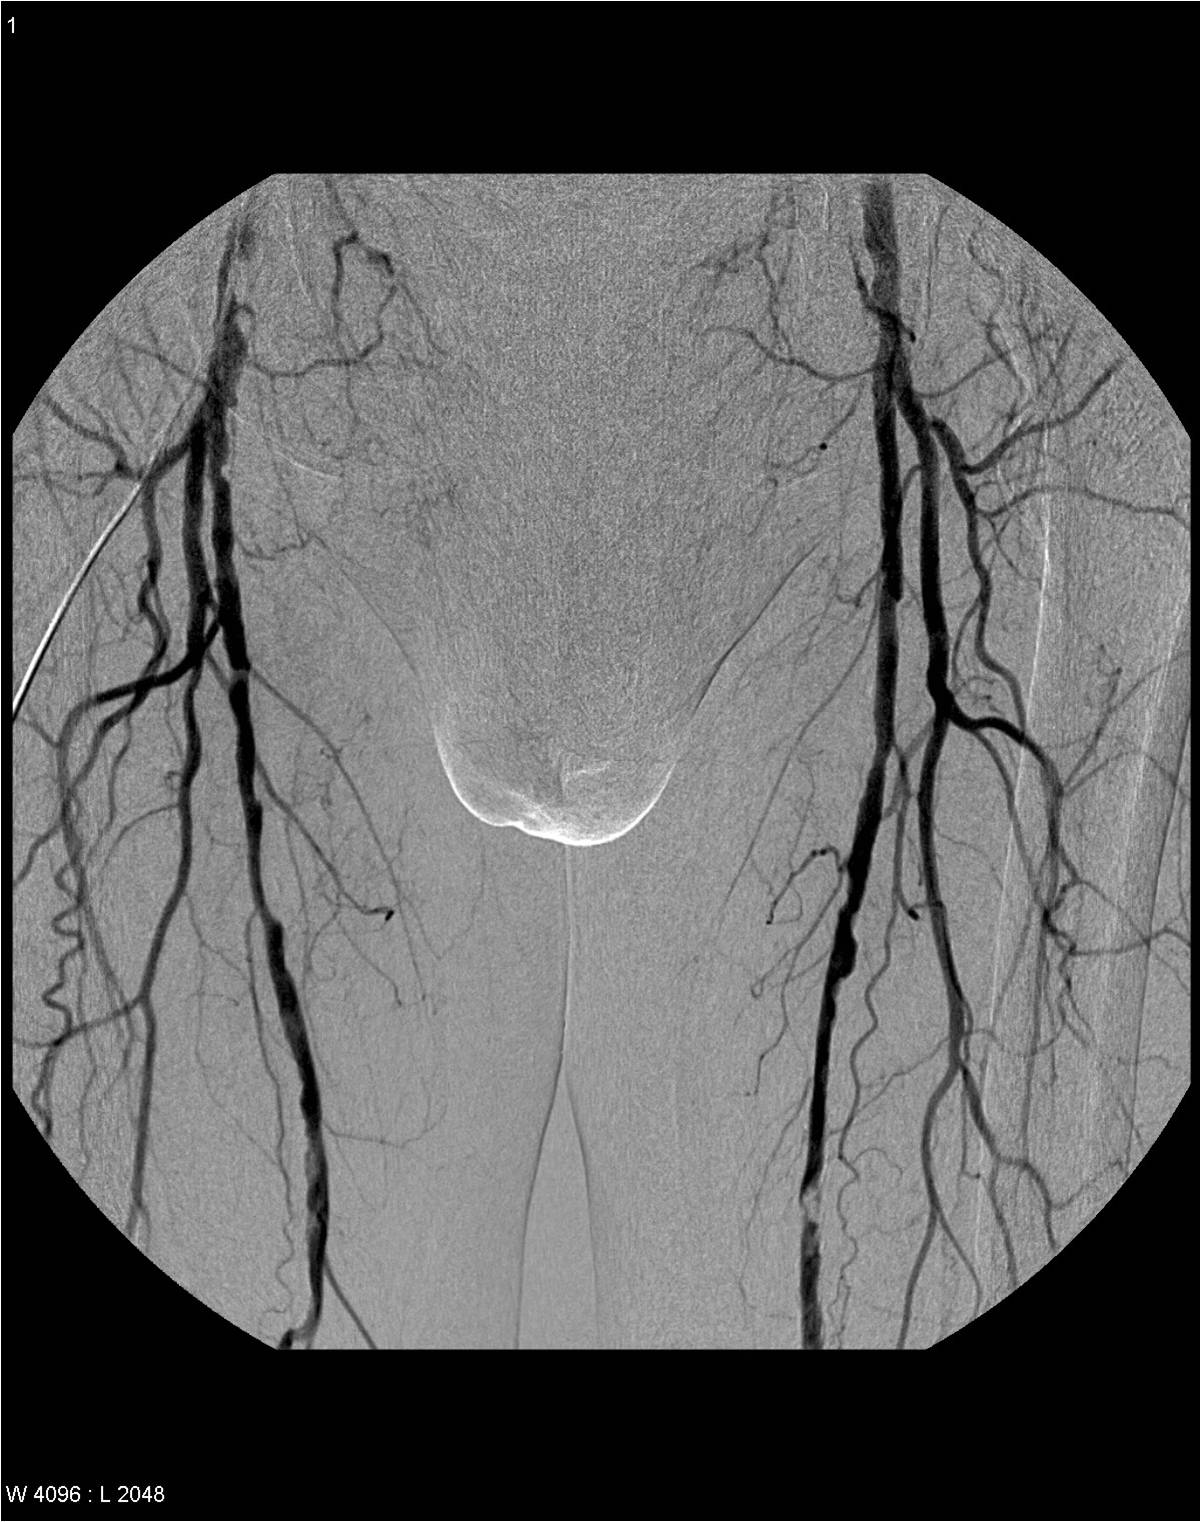

Image

Proximal aortic occlusion – Leriche’s syndrome

Bilateral multiplex femoral artery stenosis

Fig. 20., 21.: DSA examination in lower extremity obliterative arterial disease